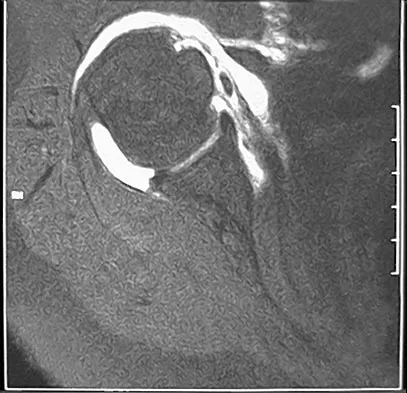

Question 99

Figures 34a and 34b show the axial and sagittal MRI scans of a 36-year-old man who reports the insidious onset of pain in the right shoulder. What is the most appropriate description of the acromial morphology?

Explanation